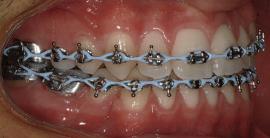

20 Dental Tribune Bulgarian Edition / октомври 2022 г. П ациентите със завършен растеж и скелетни проблеми обикновено представляват предизвикателство за ортодонт ската практика. Необходимостта от изваждане на зъби в комбинация с особеностите на възрастовата ортодонтия изисква особено внима ние. Фокусът върху критично важното значение на позицията на долните резци във връзка с дългосроч ната стабилност и постигането на оптимални оклузални взаимоотношения при затварянето на екстракционните пространства лесно може да излезе извън контрол. Когато към тези чисто кли нични проблеми се добави и стресът от натоваре ната практика, предизвикателството става още по-голямо. Всички тези фактори налагат използ ването на доказан подход с ясни и последовател ни стъпки, в което се разкрива силата на дисциплината „Алекзандър“ – предвидим протокол през целия процес на елиминиране на ротациите, ниве лиране на дъгите, затваряне на екстракционните пространства и финализиране на случая. Именно такъв е и случаят, който презентираме –екстракционен, скелетен клас 3 при възрастен па циент, лекуван по системата „Алекзандър“. ПРЕДВИДИМИ РЕЗУЛТАТИ ПРИ ПАЦИЕНТИ СЪС ЗАВЪРШЕН РАСТЕЖ И СКЕЛЕТЕН КЛАС 3, ИЗПОЛЗВАЙКИ ЕКСТРАКЦИОННО ЛЕЧЕНИЕ ПО ДИСЦИПЛИНАТА „АЛЕКЗАНДЪР“ Д-р Радой Димитров, България Преди започване на лечение клиничен случай | ортодонтия Фиг. 1а–1e Преди започване на лечение. Пациентът пристига в практиката с основното оплакване от невъзмож ност за нормално дъвчене. Снета е цялата необходима диагностична ин формация. Фиг. 1f–1h Снимки в профил и анфас. Фиг. 1i–1k Панорамна снимка, телерентгенография и анализ на телерент генография. Фиг. 1а Фиг. 1d Фиг. 1f Фиг. 1g Фиг. 1h Фиг. 1e Фиг. 1b Фиг. 1c Фиг. 1i Фиг. 1j Фиг. 1k

closed.

21Dental Tribune Bulgarian Edition / октомври 2022 г. ДИАГНОСТИЧНИ РЕЗУЛТАТИ: 1. Възраст на пациента: 21 години 2. Скелетен клас III (ANB 0) 3. Зъбен клас 3 4. Ръбцова захапка във фронта, кръстосана в дисталните участъци 5. Тясна горна челюст 6. Overjet – 0 мм, Overbite – 0 мм 7. Несъответствие на горната с долната средна линия 8. Единични контакти в ЦО 9. Хиподивергентен тип на растеж SN/MP – 33.5 10. Неравен гингивален контур 11. Неравна линия на усмивката 12. Тенденция за рецесии в долен фронт ПРЕПОРЪЧИТЕЛНО ЛЕЧЕНИЕ: Пълно ортодонтско лечение с метални брекети „Алекзандър“ Корекция на клас 3 захапката в областта на кучешките зъби с екстракция на първите пре молари в долна челюст Корекция на кръстосаната захапка в дистални участъци Коригиране на ръбцовата захапка във фронта Подобряване на ОJ и OB на пациента Стрипинг в долен фронт Подреждане на зъбите в горната и долната челюст Професионално хигиенизиране и профилактични дентални прегледи са препоръчителни на всеки 6 месеца. 1-ви месец След 1 месец са залепени брекети в горната челюст – поставена е еластична дъга. 016 NiTi. В долната челюст са елиминирани ротациите, поставена е стоманена дъга. 016SS, закалена с ток, и еластична верижка за затваряне на пространствата. 3-ти месец В долната челюст е поставена трета дъга – 17 x 25 NiTi с къси лигатури и верижка

В горната челюст се затварят пространствата с дъга .016SS и верижка. 5-и месец На 5-ия месец след залепяне на брекетите в долната челюст е поставена стоманена дъга 16 x 22 SS с четвъртито сечение, омега луп и тай бек. В горната челюст е поставена дъга 17 x 25 NiTi. Поради липсата на стабилни оклузални контакти са поставени лингвални верижки в областта на моларите, за да се предотврати нежелана ротация на 7-ите зъби. 6-и месец На 6-ия месец от началото на лечението са екстрахирани долните първи премолари, поставена е дъга 16 x 22 SS със затваряща чупка teardrop. Чупката се активира всеки месец по 1 мм с чинч-бек. клиничен случай | ортодонтия СТЪПКИ НА ЛЕЧЕНИЕТО Начало на лечението Лечението започва с поставяне на апарат за бърза експанзия в горната челюст. През първия месец от лечението са направени 24 оборота на апарата за експанзия. Залепени са брекети в долната челюст, поставена е дъга 17x25 CuNiTi, като са предпи сани клас 3 ластици (1/4”,4 1/2 oz) по време на сън, за да се осигури контрол върху торка на долните резци. Фиг. 2а Фиг. 3a Фиг. 4a Фиг. 3b Фиг. 4b Фиг. 3c Фиг. 4c Фиг. 3d Фиг. 4d Фиг. 3e Фиг. 4e Фиг. 5a Фиг. 5b Фиг. 5c Фиг. 5d Фиг. 5e Фиг. 6a Фиг. 6b Фиг. 6c Фиг. 6d Фиг. 6e Фиг. 7a Фиг. 7b Фиг. 7c Фиг. 7d Фиг. 7e Фиг. 2b Фиг. 2c Фиг. 2d

Dental Tribune Bulgarian Edition / октомври 2022 г.22 клиничен случай | ортодонтия 14-и месец В горната и долната челюст са поставени последни стоманени дъга с омега луп и тай бек – 17 x 25 SS с четвъртито сечение. Назначени е ластик за средната линия в комбинация с клас 3 ластик (1/4”, 6 1/2 oz). Контролни рентгенографии 13-и месец Екстракционните пространства са затворени. Направена е контролна панорамна снимка за оценка позицията на корените. Взето е решение за презалепване на брекетите на 12, 22 и пръстените на 36 и 46. 21-ви месец Средната линия в горната и долната челюст съвпадат. Ластиците са спрени. Свалени са пръстените и брекетите в горната и долната челюст, зигзаг ластици не са използвани поради благоприятните оклузални взаимоотношения. Фиг. 11j Ортопантомография в края на лечението. Фиг. 11k Телерентгенография след края на лечението. Фиг. 11l Анализ на телерентгенографията след лечението. Фиг. 11m Последователност на дъгите в горната и долната челюст Фиг. 11n Суперимпозиция на PreOp и PostOp ортопантомографии. 10-и месец Затварянето на пространствата е предвидимо и контролирано, без да се отварят пространства в зъбната дъга. Фиг. 8a Фиг. 8b Фиг. 8c Фиг. 8d Фиг. 8e Фиг. 10a Фиг. 10b Фиг. 10c Фиг. 10d Фиг. 10e Фиг. 9a Фиг. 9b Фиг. 9c Фиг. 9d Фиг. 9e Фиг. 9f Фиг. 11a Фиг. 11f Фиг. 11j Фиг. 11l Фиг. 11m Фиг. 11n Фиг. 11k Фиг. 11g Фиг. 11h Фиг. 11i Фиг. 11b Фиг. 11c Фиг. 11d Фиг. 11e

Dental Tribune Bulgarian Edition / октомври 2022 г. 23клиничен случай | ортодонтия реклама Лечението е продължило 21 месеца. Проведено е домашно избелване с индивидуални шини. За автора: Д-р Радой Димитров завършва с отличие Факултета по дентална медицина към МУ–София през 2015 г. В продължение на 5 години работи в няколко водещи практики в София, като през 2019 г. заедно със своята съпру га д-р Траяна Димитрова основават собствена практика в гр. Гоце Делчев –Dimitrovi Dental Care. Посещава редица курсове за повишаване на квалификаци ята, но най-сериозен тласък в развитието на ортодонтската си практика получава след завършването на комплексната ортодонтска програма, воде на от д-р Иван Горялов, базирана на дисциплината „Алекзандър“ – система с повече от 50 години опит в целия свят. Д-р Димитров е член на Българския изследователски клуб „Алекзандър“. Взе ма участие като гост-лектор в симпозиума с международно участие The Power of the Alexander Discipline, който се проведе на 14–15.05.2022 г. С д-р Ди митров можете да свържете на тел. +359885 252 025. Заключение Представеният случай е ярък пример за възможностите и красо тата на дисциплината „Алекзандър“ – приложен е утвърден под ход с ясни правила и са постигнати очакваните цели. Резулта тът ще бъде дългосрочно стабилен, тъй като са спазени всички правила, които се отнасят към максимално комфортната пози ция на зъбите в края на лечението. Постигнати са красива усмив ка и стабилна оклузия. ПОСТИГНАТИ РЕЗУЛТАТИ ОТ ЛЕЧЕНИЕТО 1. Коригирана ръбцова захапка 2. Коригирана клас 3 захапка в областта на ку чешките зъби 3. Коригирана кръстосана захапка в дисталните участъци 4. Коригиран овърджет и овърбайт 5. Разширена е горната зъбна дъга 6. Подредени зъби в горната и долната челюст 7. Постигната е стабилна захапка с множество контакти в ЦО 8. Драматично е подобрена дъвкателната функ ция 9. Подобрена е линията на усмивката ДРУГИ ПРОВЕДЕНИ ДЕНТАЛНИ ПРОЦЕДУРИ 1. Домашно избелване на зъбите 2. Екстракция на мъдреците Фиг. 12a Фиг. 12b Фиг. 12c Фиг. 12eФиг. 12d Фиг. 12f Фиг. 12g Информация за дати, цени и отстъпки www.bracescourses.com 0889 22 55 01 Практически курсове лектор д-р Иван Горялов Дисциплината „Алекзандър“ ПЪТЯТ КЪМ СУПЕРУСМИВКИТЕ 100% връщане на цялата сума, ако не сте удовлетворени след преминаване на Ниво 1 Директно и индиректно залепяне на брекети Анализ, диагноза и план на лечение Лечение на клас 2 дълбока захапка Екстракционно лечение Лечение на клас 3 отворена захапка НИВО 5НИВО 1 НИВО 2 НИВО 3 НИВО 4